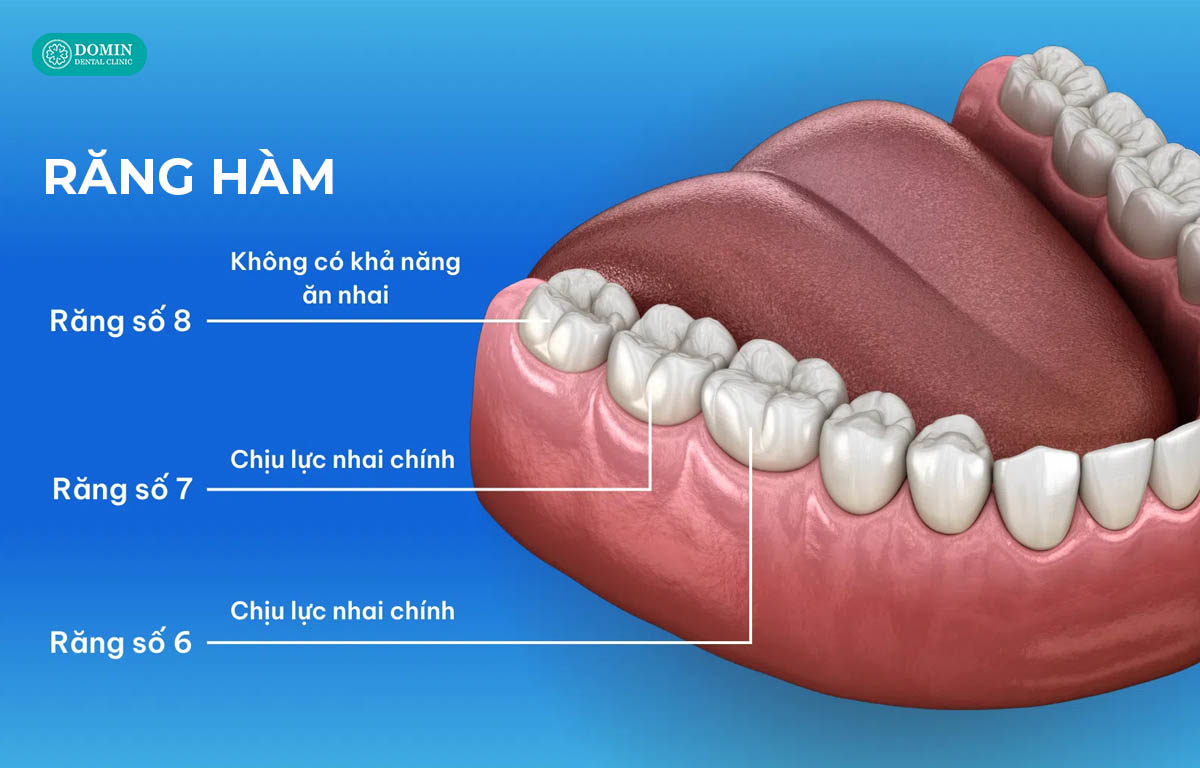

Răng hàm là nhóm răng nằm ở phía trong cung hàm, giữ vai trò chính trong việc nhai và nghiền nát thức ăn. Bề mặt răng hàm có nhiều múi và rãnh sâu, giúp tăng diện tích tiếp xúc khi nhai nhưng cũng khiến việc vệ sinh khó hơn, dễ tích tụ mảng bám và vi khuẩn.

Về cấu trúc, răng hàm có men răng dày và cứng, bên dưới là lớp ngà răng và hệ thống chân răng vững chắc, giúp răng chịu được áp lực nhai rất lớn. Ở vùng hàm dưới, lực nhai có thể lên tới hàng trăm kilogram, vì vậy nhóm răng này luôn cần độ bền cao.

Ngoài ra, do nằm sâu trong khoang miệng và gần vùng khớp thái dương, hàm, răng hàm còn chịu ảnh hưởng trực tiếp từ khớp cắn và hoạt động cơ nhai. Chỉ cần khớp cắn sai hoặc thói quen nghiến răng, nhóm răng này dễ bị mòn, nứt hoặc ê buốt.

Về nguyên tắc, răng hàm vẫn có thể dán veneer, nhưng điều quan trọng là phải hiểu rõ đặc thù của nhóm răng này trước khi quyết định. Răng hàm có bề mặt nhai rộng, nhiều múi và rãnh, đồng thời chịu lực nhai lớn hơn rất nhiều so với răng trước. Vì vậy, bất kỳ vật liệu phục hình nào đặt lên răng hàm đều phải đủ bền, đủ cứng và được kiểm soát khớp cắn chính xác.

Ngược lại, với những răng hàm lớn (răng số 6, 7), vùng chịu lực nhai chính, veneer không phải là lựa chọn lý tưởng. Thay vào đó, phục hình Onlay/ Inlay sẽ phù hợp hơn. Hai phương pháp này giúp phục hồi phần mặt nhai bị sứt, mòn hoặc vỡ lớn, vẫn bảo tồn mô răng thật mà đảm bảo khả năng chịu lực gấp nhiều lần veneer.